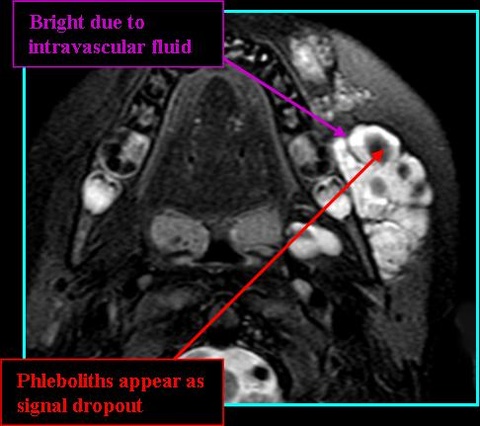

- MR:

- T2: high signal with differing apprearance based on vein diameter, phleboliths appear as dropped signal

- T1 post-contrast MR: highly variable signal - hypo- to hyperintense, homogenous or heterogeneous signal